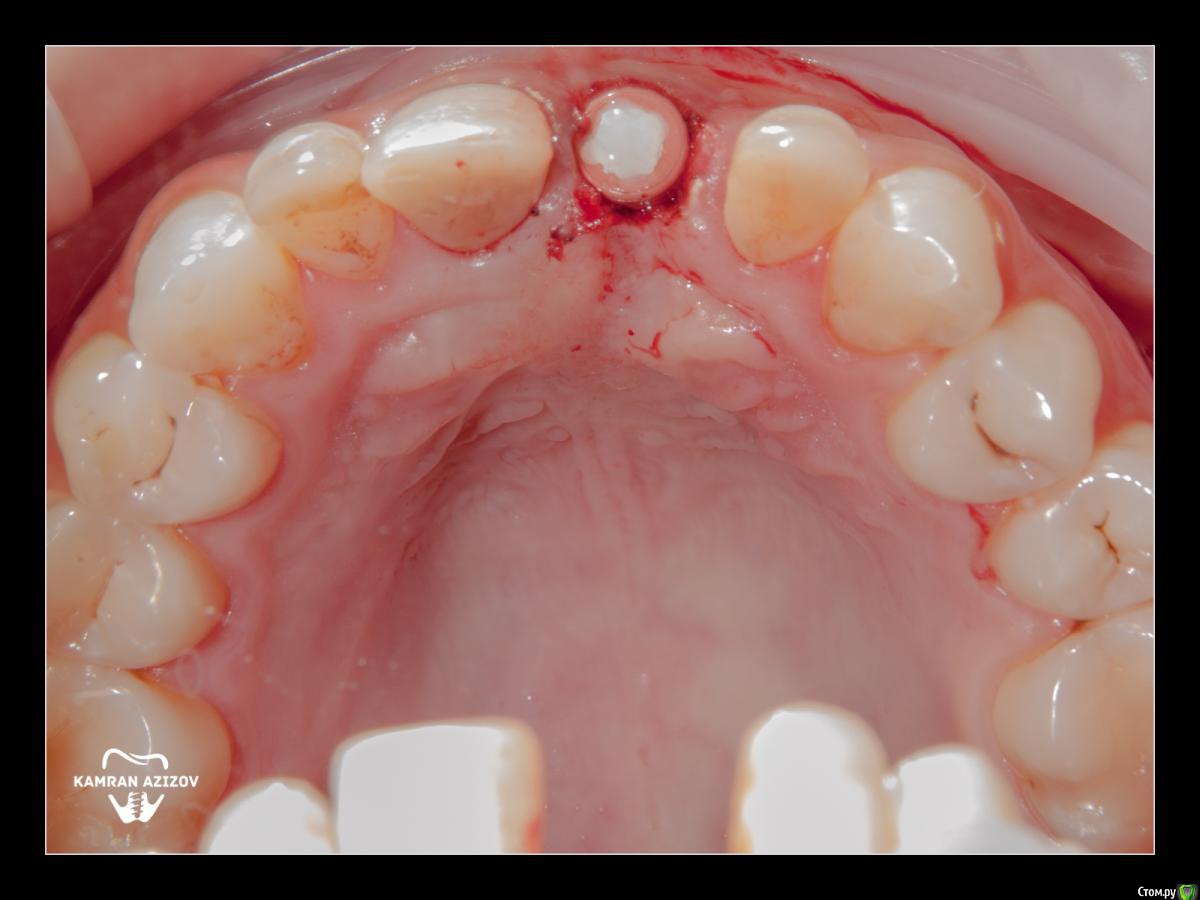

kamranchick Опубликовано 8 октября, 2019 Поделиться Опубликовано 8 октября, 2019 удаление зуба+консервация лунки с вестибулярным ССТчерез 2 месяца имплантация с фдм по карлоссучерез 4 месяца замена на более длинный фдм и широкийпостоянная коронка 5 Ссылка на комментарий

Nazim_NV86 Опубликовано 10 октября, 2019 Поделиться Опубликовано 10 октября, 2019 посмотрел только последнюю фотку. Такая зпкд всё прощает Ссылка на комментарий